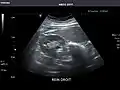

Kidneys: Right and left kidneys measure 11.5 cm and 12 cm in length respectively. No hydronephrosis. Small left lower pole kidney cyst.

Right kidney -